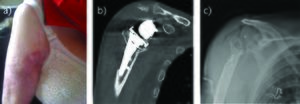

Shoulder resection should remain a salvage procedure for frail or low-demand patients and recalcitrant infection. It offers the option of a single definitive procedure for infection eradication (Figure 2). It has been shown that functional results are poor, but pain relief is achieved in more than 50% of cases.[10][45] Rispoli et al. reported a mean active elevation of 70 degrees at long-term follow-up after anatomical shoulder arthroplasty removal.[45] Verhelst et al. demonstrated that preservation of the tuberosities is a predictive factor for better results, because it can avoid antero-superior subluxation of the humerus.[2] In cases of reverse shoulder arthroplasty, Jacquot et al. did not improve functional outcomes after removal of the implant and identified a high rate of post-operative complications.[29] Bone loss and soft-tissue impairment after such constrained prostheses could partly explain these findings. Despite Jacquot[29] and Coste’s[27] studies, the literature reports a high rate of infection eradication reaching more than 90% of cases.[2][10][27][30] [46][47]

Figure 2. Radiographs (A and B) of an 86-year-old woman, with a loose implant secondary to chronic periprosthetic shoulder infection. C) Because of numbers of co-morbidities and huge bone loss on glenoid side, a simple resection arthroplasty was performed.From Bonnevialle et al.,[1] with permission.